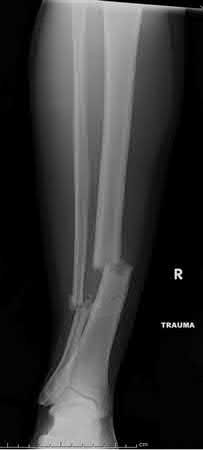

Orthopedic Ob Trauma Review | Dr Hutaif Trauma & Fractu -...